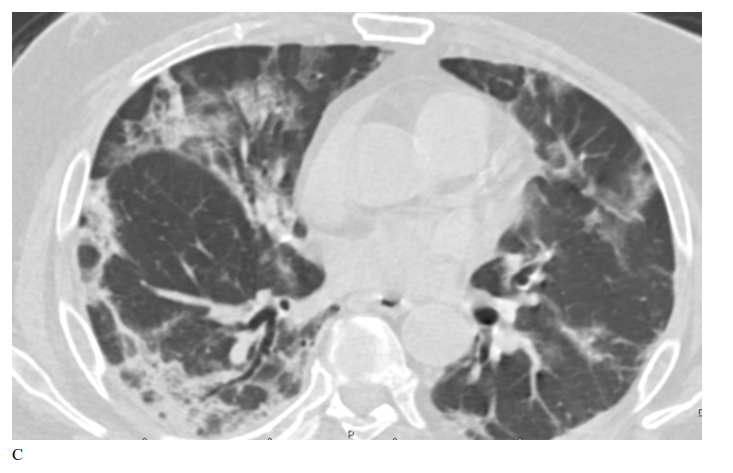

Figure 2: Male patient in remdesivir group shows bilateral ground glass opacities affecting mainly upper lobes and pleural based with small areas of atelectatic bands, Covid severity score 18, while figure D 3 months after treatment shows marked improvement of already present infiltrates with Covid severity score 8.